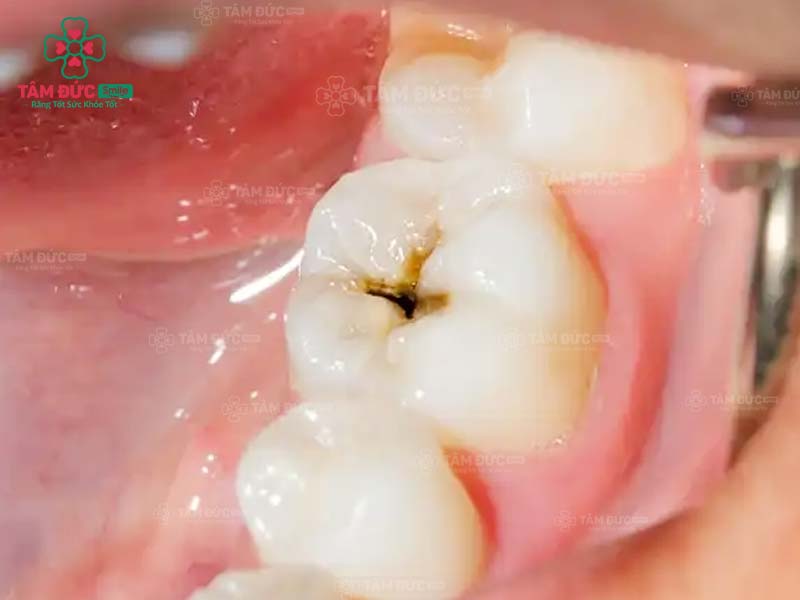

1.1. Răng bị sâu

Khi răng bị sâu, trên thân răng xuất hiện các lỗ nhỏ li ti. Đây chính là vị trí trú ngụ của hàng nghìn loại vi khuẩn. Cùng với thói quen chăm sóc răng miệng không tốt, ăn thực phẩm chứa nhiều đường, lỗ sâu răng sẽ lớn dần và gây đau nghiêm trọng. Nguy hiểm nhất chính là nhiễm trùng và mất răng vĩnh viễn.

Trám răng giúp lấp đầy các lỗ hổng trên thân răng. Nhờ đó, các triệu chứng khó chịu, biến chứng do răng sâu được loại bỏ triệt để. Thẩm mỹ của chiếc răng bị sâu nói riêng và cả hàm răng nói chung đều được phục hồi.